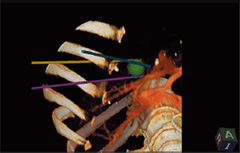

Real-time Virtual Sonography(RVS)

・3D Sim-Navigator

単数・複数本穿刺の際に,RVSでターゲットへのナビゲーションをしながら,穿刺ラインをシミュレーションします。

CTなどのボリュームデータから作成した3Dボディマークと,穿刺ラインとの直交断面を表示するC-planeを利用することにより,マークしたターゲットと穿刺ラインの位置関係をリアルタイムに三次元的に把握できます。

・E-field Simulator

RFA治療時の電極の配置から決定される電気的物理量(電場)をCTなどの画像上に表示します。複数本穿刺の際にもあらゆる電極配置に合わせて電場をシミュレーション可能なので,穿刺ライン検討の自由度が大幅に高まります。

これまでの手技を大幅に改善することが期待されます。